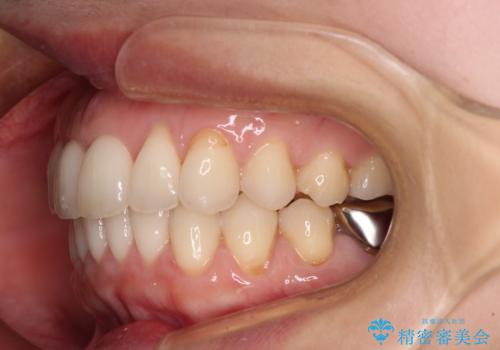

- 上下の前歯のデコボコを気にして来院された患者様です。

上下顎歯列全体の後方移動とIPR(歯と歯の間を削る)によってデコボコが解消するように設計しました。